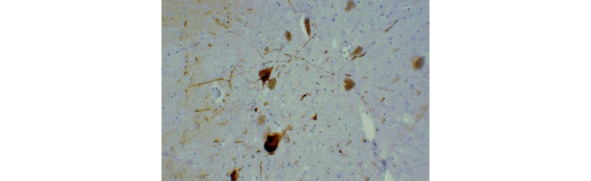

В основе патогенеза развития БП лежит повреждение дофаминергических нигростриарных нейронов и накопление альфа-синуклина (αSyn), содержащихся в тельцах Леви. Альфа-синуклеин является основным компонентом телец Леви. Нарушение процессинга αSyn является центральным звеном молекулярного патогенетического каскада, ведущего к накоплению в клетке нерастворимых белковых комплексов и прогрессирующей дегенерации соответствующей популяции нейронов при БП. Еще в 1919 году советский невропатолог Константин Николаевич Третьяков (рис. 3) связал развитие симптомов паркинсонизма с утратой пигментных нейронов черной субстанции ствола, а также с накоплением в этих клетках патологических включений (рис. 4). Нейрональные включения К. Н. Третьяков предложил называть тельцами Леви в честь немецкого морфолога Фридриха Леви, который ранее описал схожие изменения при паркинсонизме в других отделах ствола мозга.